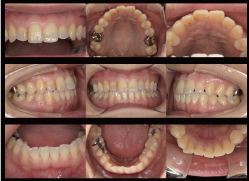

口腔内写真

すべての患者さんに初診や治療中のお口の中の

写真を撮影します。最初の状態や問題点または歯

ブラシによる歯肉の変化や治療の成果・経過を鏡

で見えない裏側まで患者さんご自身に見ていた

だくことができます。

口腔内写真により状態を確認